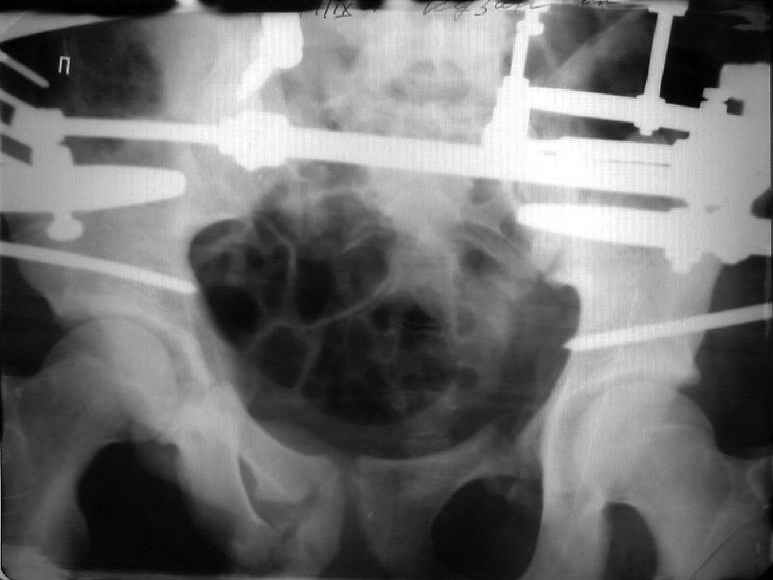

Re: Застарелый перелом таза

Для информации к размышлению о возможности исправления имеющейся деформации предлагаю похожий случай.